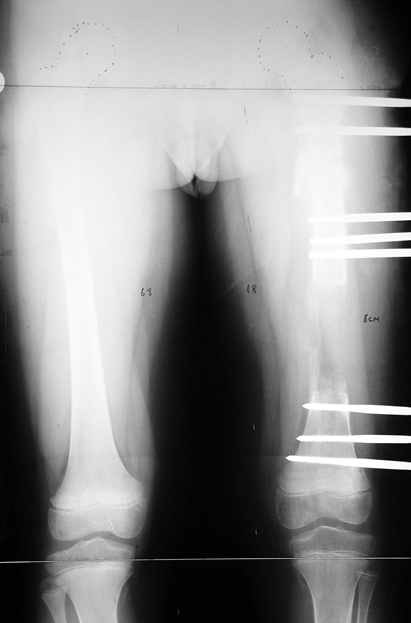

Appropriate radical debridement necessitates excision of all necrotic bone and soft tissues, and frequently causes instability at the involved extremity. The remaining bone and soft tissue defect has to be fixed and reconstructed. The distraction osteogenesis method of Ilizarov is used successfully for achievement of union, correction of the deformity, elimination of limb length inequality and reconstruction of segmental bone defects.

The duration of external fixation (external fixation index) depends on the amount of distraction required, and the extremity is prone to complications during this period. After the distraction phase is completed, the external fixator remains in place during the consolidation phase, which lasts twice as long as the distraction phase; but this period is hardly tolerated. If the external fixator is removed before sufficient consolidation is achieved, fractures, deformity and shortness will be the result. In our department, ‘lenghthening over nail’ method is used in order to decrease the external fixation index and increase patient comfort and activity level. In this method, the intramedullary nail is statically locked after the completion of the distraction phase, and external fixator is removed. The extremity is stabilized by the intramedullary nail during consolidation phase. In this way, complications due to long external fixation index or early removal of the external fixator are avoided.